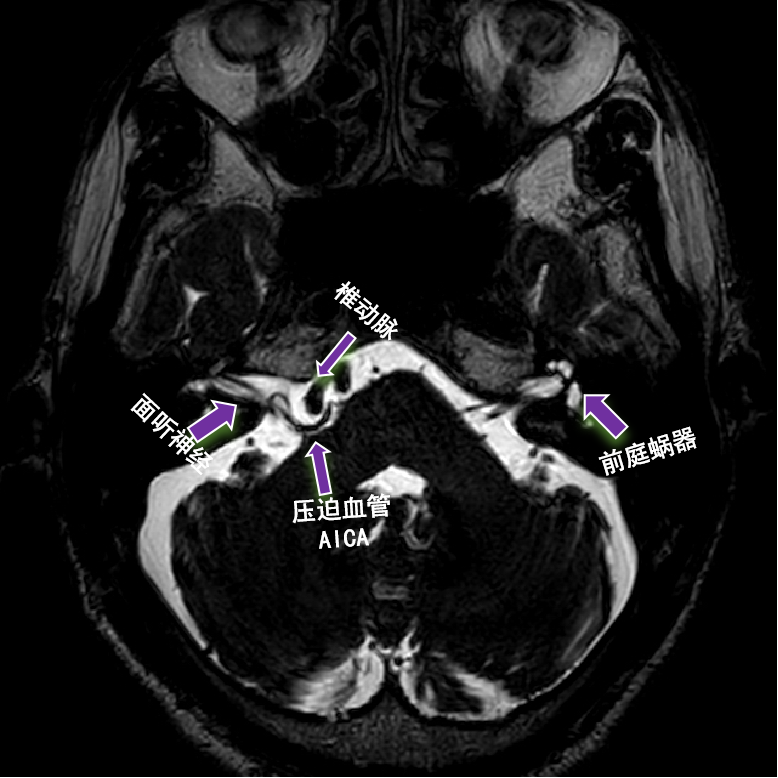

患者颅脑核磁影像

结合神经内科主治医师王也安排的影像检查,神经外科脑神经损伤修复门诊主治医师张培海判断患者应为右侧小脑前下动脉(AICA)压迫面听神经所致。“电生理监护下的微血管减压术是目前国际公认的治疗方法,通过推开压迫血管,解除面神经压迫问题。”张培海说,“目前该手术已经实现数智化规划,在虚拟三维空间中通过不同角度观察神经、血管及静脉窦等重要结构的关系,明确微血管减压手术具体步骤及遇到的解剖结构、标志,进行精准的面听神经与责任血管减压,减少不必要的损伤,最大程度提高手术安全性。”